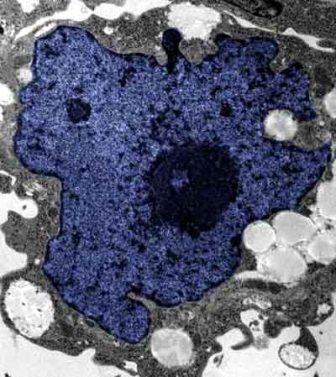

在成人體內(nèi)及胚胎內(nèi)發(fā)現(xiàn)的干細胞屬于主細胞,能發(fā)育成各種各樣的組織,可作為人體“修補工具箱”,取代死去及腐壞細胞組織。此前,最可行的干細胞為胚胎干細胞,但它的使用一直受到爭議,因為要在胚胎抽取干細胞會令胚胎死亡,有人認為這樣是變相奪走一條生命。

2007年,日本京都大學教授山中伸彌為首的科研小組證明,利用病毒倒撥普通皮膚細胞的“生理時鐘”,可把它們變成像胚胎干細胞那樣具備“變身”能力的細胞。但利用病毒把基因輸入細胞,有可能導致癌癥。這即是說使用這些細胞的風險很大。

來自英國和加拿大的兩組研究員所用的新方法不必使用病毒。這項新突破暗示科學家現(xiàn)在能更認真地看待在醫(yī)學中利用皮膚干細胞(即誘導多功能干細胞,俗稱“iPs”細胞)的前景。

這些細胞只要配以適當?shù)幕瘜W品和蛋白質(zhì),就能轉(zhuǎn)化成腦神經(jīng)元、制造胰島素的胰腺細胞、骨或軟骨、心臟肌肉,或其它多種組織。這些細胞利用病人皮膚來培育,更暗示它們不會被人體排斥。